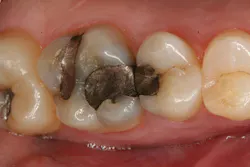

The clinical case in Figure 3 illustrates a patient who presented with a large, failing restoration containing cracks and decay. The patient was interested in an all-ceramic restoration. Occlusion was checked with articulating paper prior to treatment with a CAD/CAM restoration (figure 4). All previous restorative materials were removed from the tooth (figure 5). The tooth was restored using Grandio Core Dual Cure (Voco) build-up material (figure 6). A crown preparation was completed for a chairside CAD/CAM crown using the CEREC system (Dentsply-Sirona). The material of choice for this restoration was IPS e.max CAD (Ivoclar Vivadent), which is seen in Figure 7 after milling and in precrystallization form. The restoration was tried in and then polished, glazed, and placed in the oven for crystallization. The internal surface was then etched with 4.9% hydrofluoric acid, rinsed, and then coated with a silane coupler to create an optimal surface for bonding with the resin luting agent. The tooth was isolated and cleaned prior to etching. Once etched, the adhesive bonding agent (Futurabond U) was activated to mix the two liquids within the single-dose blister package. The blister seal was broken with the bonding agent brush and the adhesive was applied and agitated for 20 seconds. The adhesive was lightly dried for five seconds and then cured with an LED curing light for 10 seconds. A dual-cured adhesive resin luting agent (Bifix QM) was dispensed into the crown with its automix syringe (figure 8). The crown was seated and excess cement was removed after a two-second light cure. The tooth was then flossed and occlusion was checked (figure 9). The patient was very satisfied with the final result.

Figure 3: A large, failing restoration containing cracks and decay